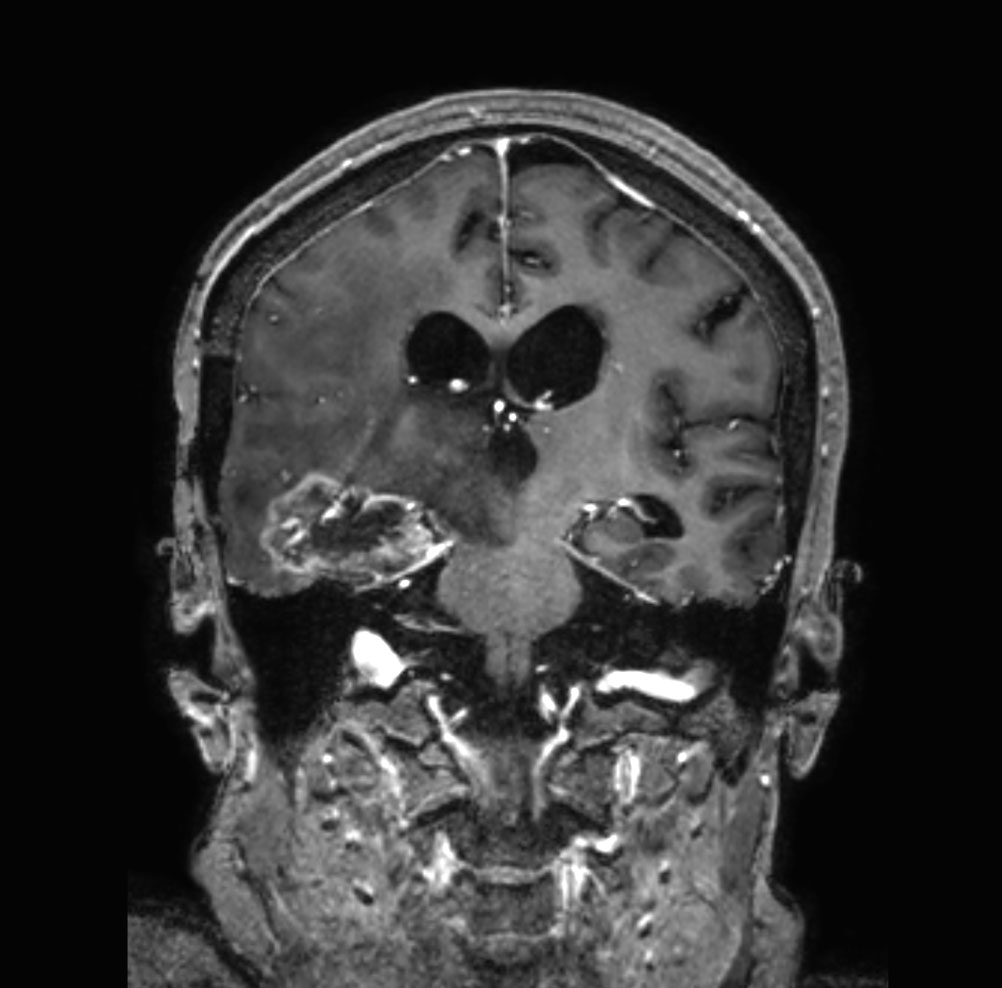

T1w 3D TFE with gado (coronal reformat)

-